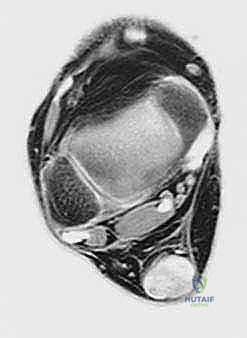

لفهم عبقرية هذه الجراحة، يجب أن نفهم التشريح. وتر العضلة المثنية الطويلة لإبهام القدم (Flexor Hallucis Longus - FHL) هو وتر يمر في الجزء الخلفي من الساق، قريباً جداً من وتر أخيل، ويمتد نزولاً ليتحكم في حركة انثناء إصبع القدم الكبير.

2. التوافق الحركي (In-phase synergy): تنقبض عضلة FHL في نفس الوقت الذي تنقبض فيه عضلات السمانة (التي تحرك وتر أخيل) أثناء دورة المشي، مما يجعل نقلها طبيعياً جداً للجهاز العصبي الحركي.

3. القرب التشريحي: يقع وتر FHL مباشرة بجوار وتر أخيل، مما يسهل عملية النقل الجراحي دون الحاجة لشقوق جراحية واسعة في أماكن بعيدة.

5. نقل وتثبيت الوتر (Tenodesis & Fixation)

هنا يتجلى الفن الجراحي. يتم حفر نفق صغير جداً في عظم الكعب (Calcaneus). يُسحب وتر FHL القوي ويُزرع داخل هذا النفق العظمي. يتم تثبيته باستخدام مسمار تداخلي حيوي (Bio-interference screw) يندمج مع العظم بمرور الوقت، مما يوفر تثبيتاً صخرياً قوياً.